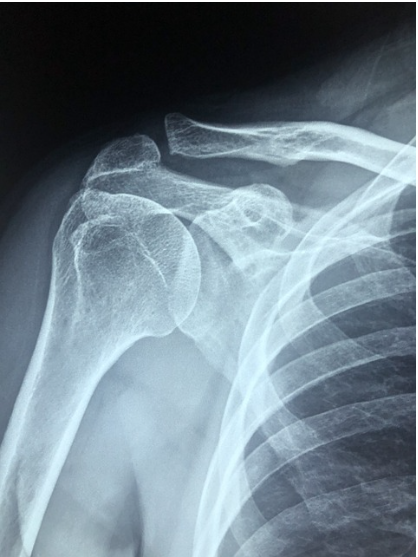

3. 진단

오십견: 주로 병력 청취와 신체 검사를 통해 진단하며, X-ray나 MRI 검사가 필요할 수 있습니다.

회전근개파열: 신체 검사와 함께 MRI 검사를 통해 회전근개 힘줄의 상태를 확인합니다.